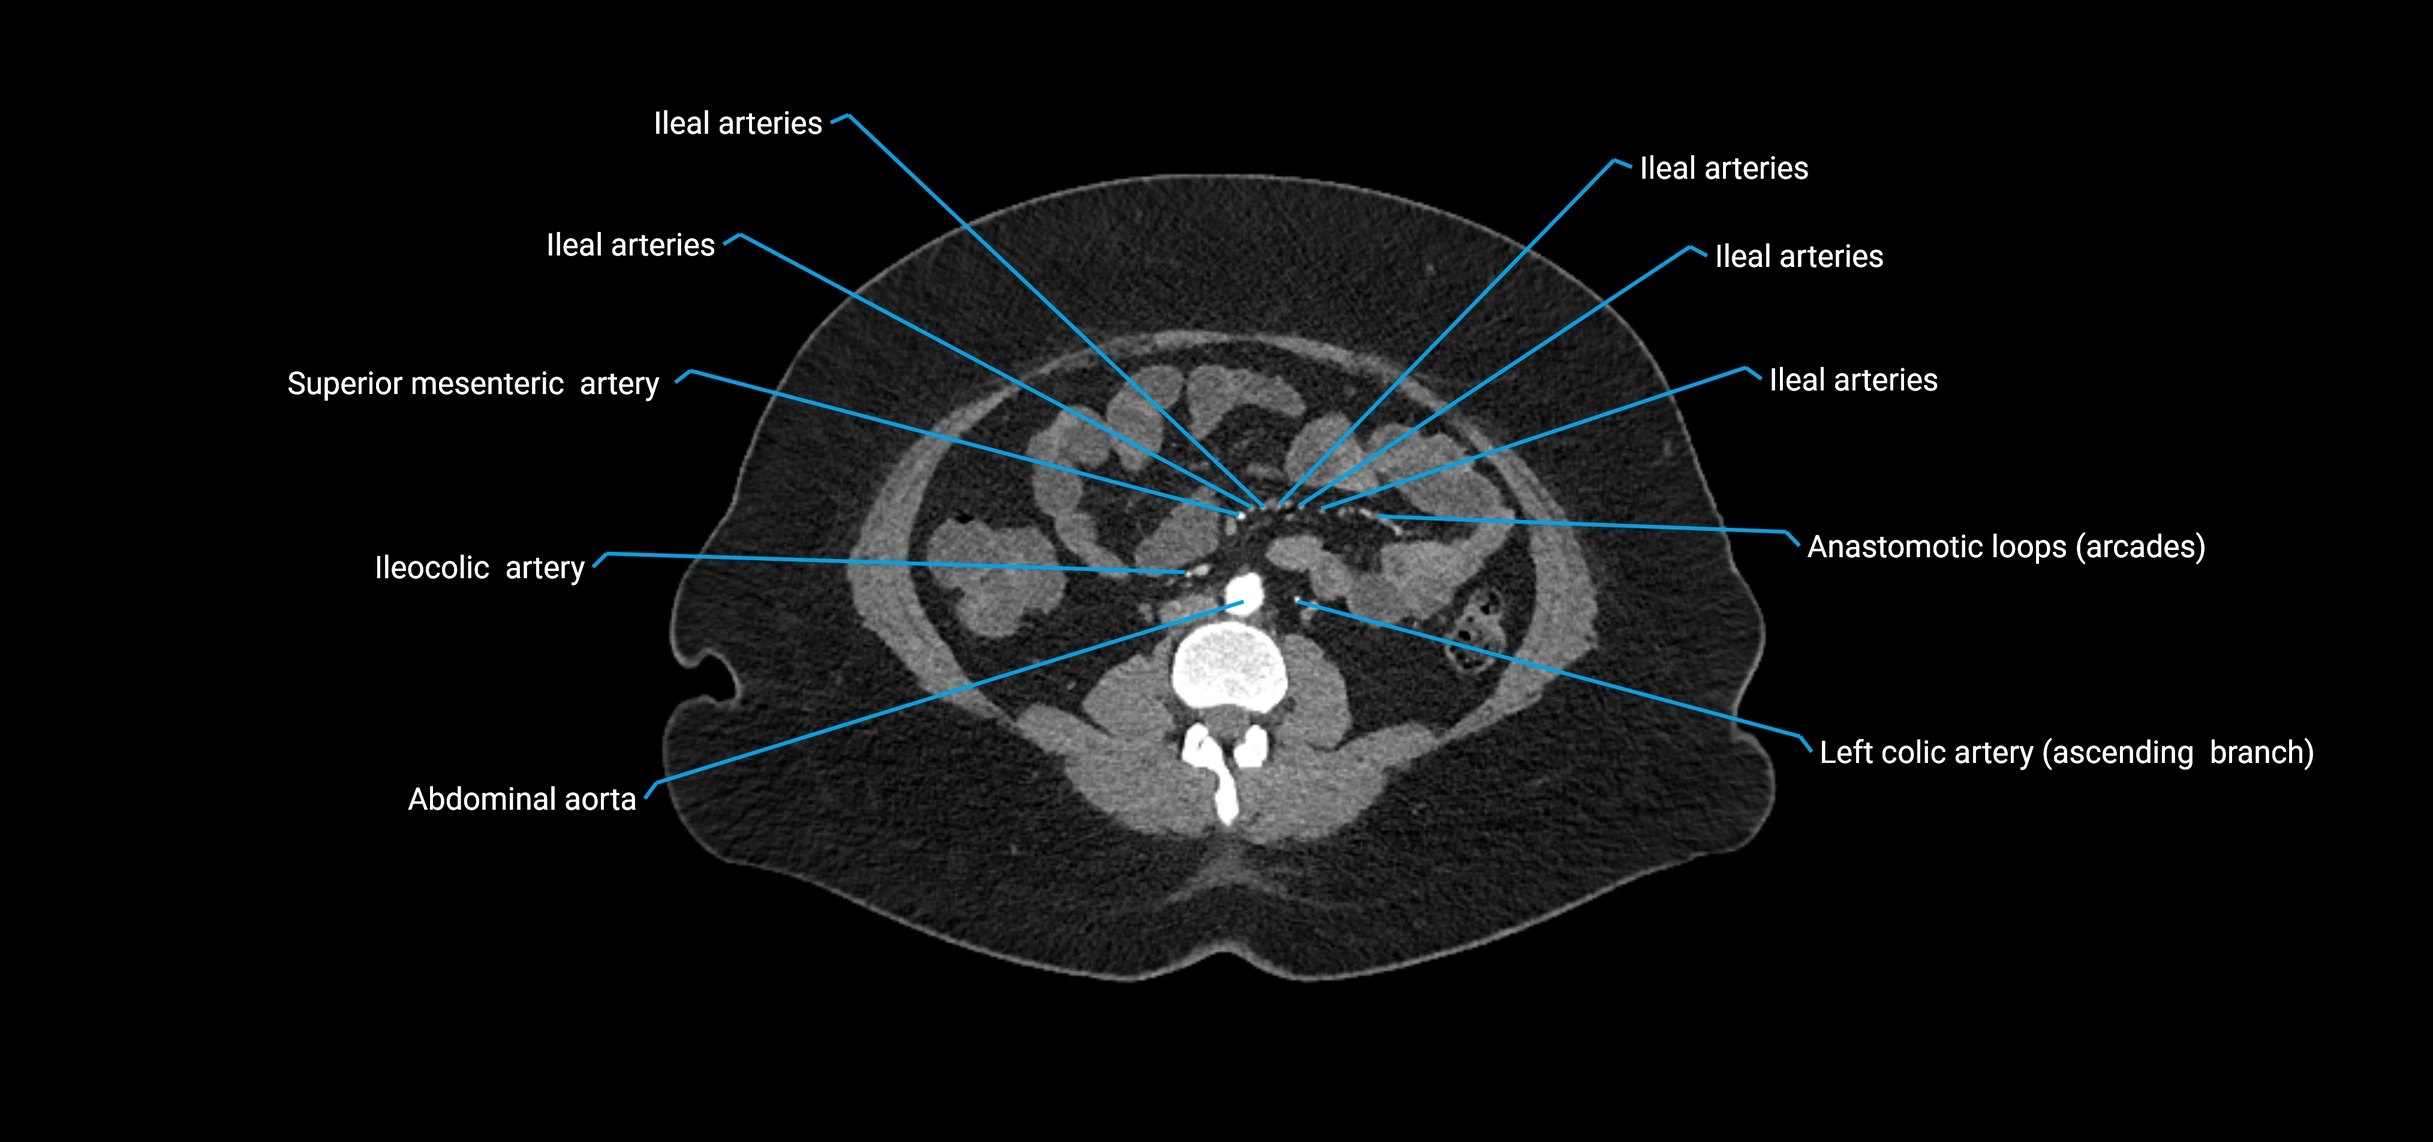

CT Appearance

Non-contrast CT:

• Appears as a tubular soft tissue structure anterior to vertebral bodies

• Calcified atherosclerotic plaques appear as hyperdense foci along the wall

• Useful for screening abdominal aortic aneurysm (AAA) size and mural calcification

Contrast-enhanced CT (CTA):

• Gold standard for abdominal aortic imaging

• Provides excellent detail of lumen, wall, aneurysm, thrombus, and branch vessels

• Multiplanar and 3D reconstructions help in aneurysm measurement, stent graft planning, and dissection evaluation

• Detects acute rupture, traumatic injury, or occlusion with high sensitivity

CT images

image